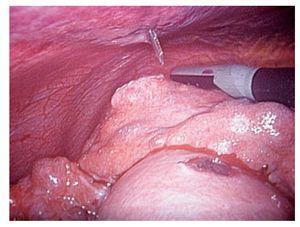

La evaluación de la respuesta al tratamiento se realizó por medio de tomografía computadorizada y marcadores tumorales. Se observó una respuesta total en 33.3% de los casos con evidencia de necrosis tumoral en más del 70% de la lesión mediante el uso de tomografía dinámica (Figura 2 y 3). En 66% de los pacientes hubo disminución significativa de los niveles séricos del marcador tumoral (alfa-fetoproteína o antígeno carcinoembrionario). Los niveles iniciales promedio de alfa-fetoproteina fueron de 169,122 ng/mL (rango 2 a 1 349 200 ng/mL) que contrastaron con los niveles promedio postratamiento de 35,081 ng/mL (rango: 2 a 463 000 ng/mL). Cabe mencionar que en esta serie de pacientes no se utilizó tratamiento neoadyuvante o adyuvante.

Figura 2. Tomografía de hígado donde se observa hepatocarcinoma unifocal en el segmento IV del hígado al momento del diagnóstico

Figura 3. Tomografía de hígado donde se observa al mismo paciente un mes después de la ablación por radiofrecuencia